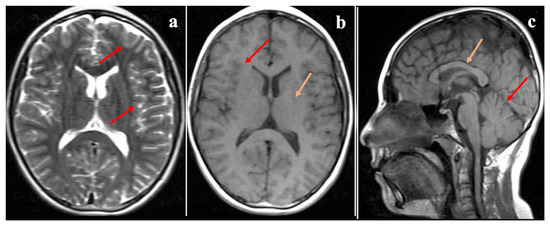

Marinesco–Sjögren Syndrome: A Novel SIL1 Variant with In Silico Analysis and Review of the Literature

by Elif Sibel Aslan, Sajjad Eslamkhah, Nermin Akcali, Cuneyd Yavas, Lutfiye Karcioglu Batur, Esma Sengenc and Adnan Yüksel

Life 2025, 15(12), 1855; https://doi.org/10.3390/life15121855 - 2 Dec 2025

Marinesco–Sjögren syndrome (MSS) is a rare autosomal recessive disorder characterized by cerebellar ataxia, congenital cataracts, developmental delay, hypotonia, and progressive myopathy. Most reported cases are linked to pathogenic variants in SIL1, a gene encoding a co-chaperone essential for protein folding in the endoplasmic reticulum. Here, we present a comprehensive case study of a Turkish pediatric patient diagnosed with MSS, supported by genetic, bioinformatic, and structural modeling analyses. Whole-exome sequencing revealed a homozygous splice-site variant (SIL1 c.453+1G>T), confirmed by Sanger sequencing and segregation analysis. In silico annotation using Genomize, InterVar, Franklin, VarSome, ClinVar, OMIM, and PubMed classified the variant as pathogenic according to ACMG guidelines. Structural modeling by Phyre2 and I-TASSER demonstrated that the variant abolishes the intron 5 donor site, leading to truncation of the wild-type 461-amino-acid protein into a shortened ~189-amino-acid polypeptide. This truncation results in the loss of critical Armadillo (ARM) repeats required for HSPA5 interaction, explaining the observed instability and impaired chaperone function. Clinically, the patient presented with congenital cataracts, ataxia, developmental delay, and progressive muscle weakness, consistent with previously reported MSS cases. Comparison with the literature confirmed that splice-site variants frequently correlate with severe phenotypes, including early-onset ataxia and cataracts. This report highlights the importance of integrating genomic, structural, and clinical data to better understand genotype–phenotype correlations in MSS. Our findings expand the mutational spectrum of SIL1, reinforce the role of splicing defects in disease pathogenesis, and emphasize the necessity of comprehensive molecular diagnostics for rare neurogenetic syndromes. Full article

Figure 1